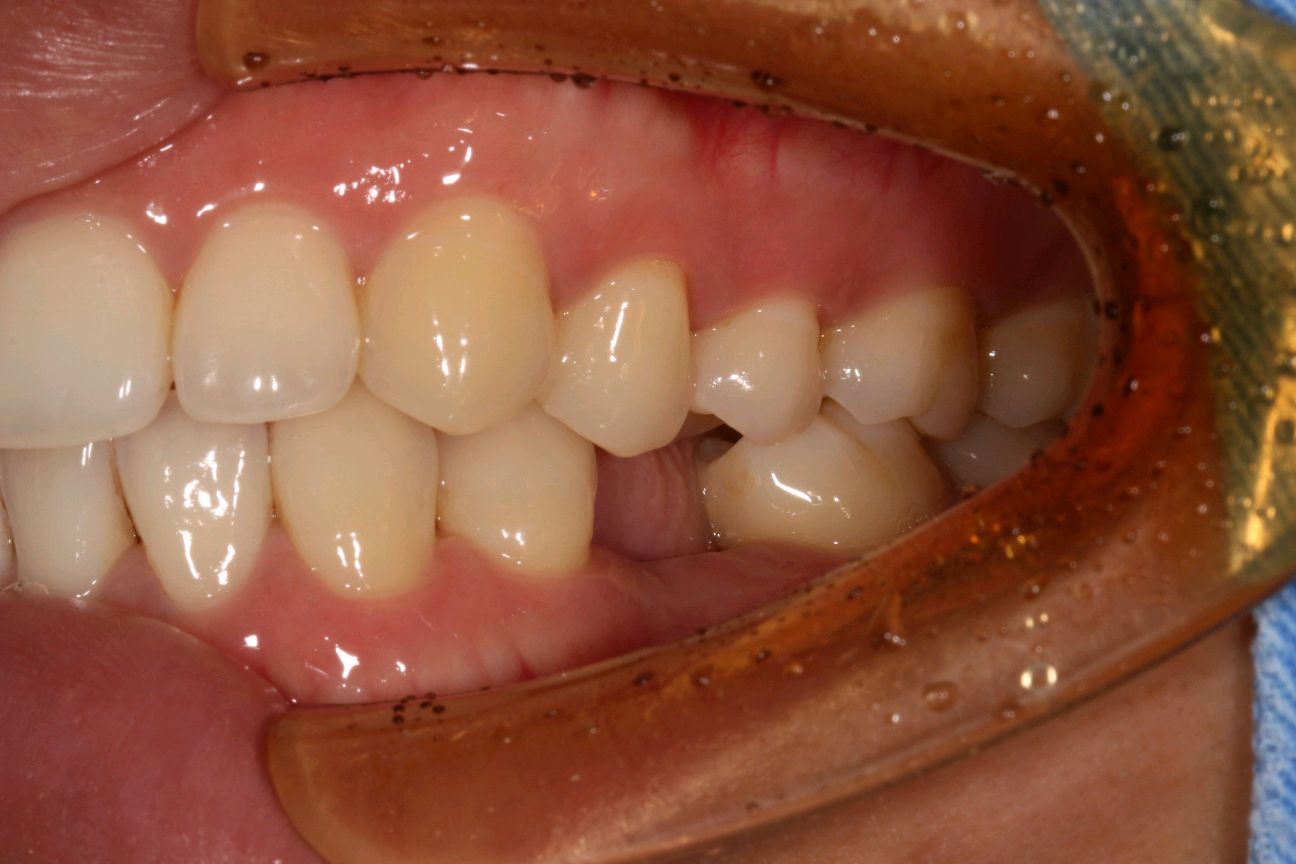

患者女三十岁,35畸形中央尖折断,根尖周炎症感染,导致牙根发育停止,根尖口呈喇叭口状。拔出后搔刮牙槽窝,颊侧骨壁吸收,植入骨粉骨膜。定期复查,将近半年见骨密度良好,骨量充足的条件下,行种植手术。植入3I 4/3*11.5mm的种植体。二期三期如期进行,与今日戴牙,患者满意。